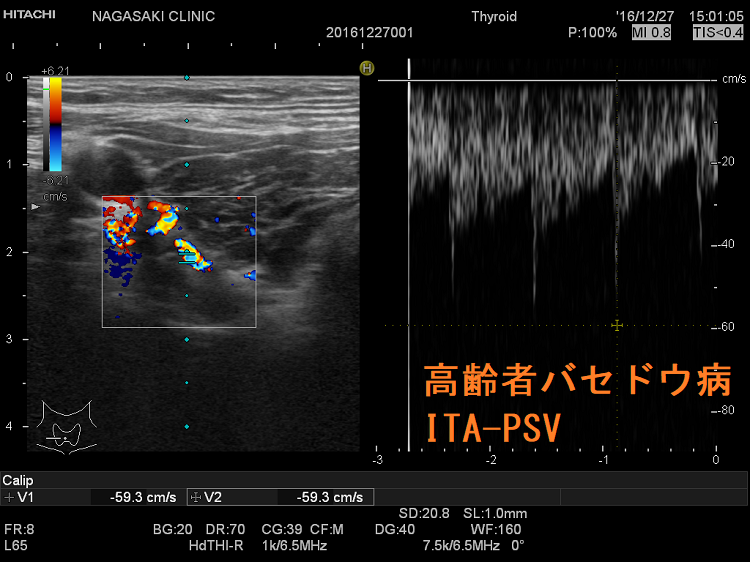

下甲状腺動脈血流(ITA-PSV)測定

甲状腺機能亢進症/バセドウ病の再発予測は、甲状腺専門医でも難しいとされます。しかしそれは、TSHレセプター抗体(TSH Receptor Antibody:TRAb)などの自己抗体を予測の指標にしているところに問題があります。TRAbは再発の指標にはなりません。

長崎甲状腺クリニック(大阪)院長が、大阪市立大学(現、大阪公立大学) 代謝内分泌内科で行った研究では、甲状腺へ流入する下甲状腺動脈の収縮期最大血流速度(ITA-PSV)を測定することにより

- 甲状腺機能亢進症/バセドウ病が再発する可能性

- 抗甲状腺薬(メルカゾール、プロパジール、チウラジール)が効きやすい甲状腺機能亢進症/バセドウ病か否か

を予測できます。

下甲状腺動脈血流速度(ITA-PSV)測定 をご覧ください。

高齢者甲状腺機能亢進症/バセドウ病は、若年性バセドウ病、中年性バセドウ病と異なる症状を呈します[Arch Intern Med. 1988 Mar;148(3):626-31.]。甲状腺が腫れにくい(甲状腺が小さい)ため、甲状腺の病気が見逃され易い[バセドウ抗体(TRAb)に対する反応性低下のため]。